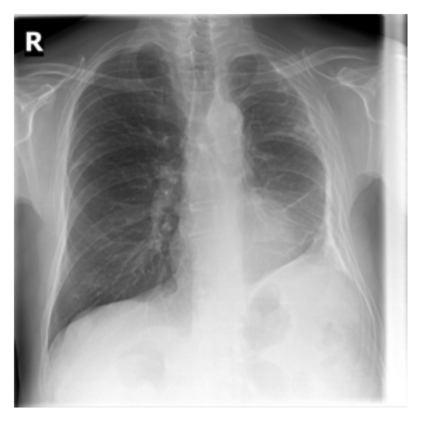

The evaluation of infectious disease processes on radiologic images is an important and challenging task in medical image analysis. Pulmonary infections can often be best imaged and evaluated through computed tomography (CT) scans, which are often not available in low-resource environments and difficult to obtain for critically ill patients. On the other hand, X-ray, a different type of imaging procedure, is inexpensive, often available at the bedside and more widely available, but offers a simpler, two dimensional image. We show that by relying on a model that learns to generate CT images from X-rays synthetically, we can improve the automatic disease classification accuracy and provide clinicians with a different look at the pulmonary disease process. Specifically, we investigate Tuberculosis (TB), a deadly bacterial infectious disease that predominantly affects the lungs, but also other organ systems. We show that relying on synthetically generated CT improves TB identification by 7.50% and distinguishes TB properties up to 12.16% better than the X-ray baseline.